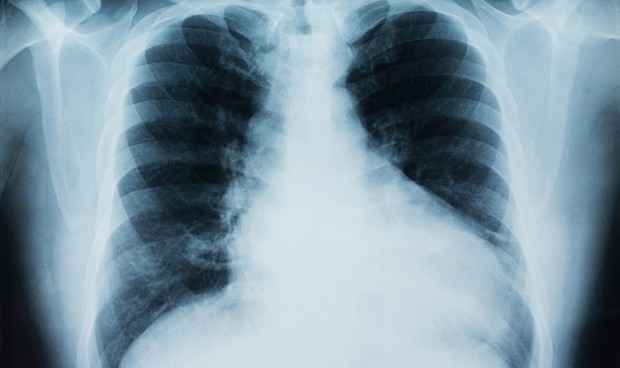

El SARS-CoV-2 activa en las células pulmonares una respuesta inmune “inesperada”, en palabras de los autores de un estudio publicado en Science Immunology, que los lleva a pensar que esté relacionada con la afectación a dicho órgano y la gravedad de la enfermedad.

Se trata del sistema inmune del complemento, un conjunto de proteínas que se derivan del hígado y que normalmente colaboran con los anticuerpos para luchar contra patógenos presentes en el torrente sanguíneo.

Sin embargo, “se halló inesperadamente que el sistema del complemento era una de las rutas intracelulares más altamente inducidas por la infección de SARS-CoV-2 en las células pulmonares epiteliales”, explica el equipo liderado por Bingyu Yan, del Departamento de Bioquímica de la Universidad de Purdue, en Estados Unidos.

La infección en estas células generó la activación de la molécula C3a, que forma parte del sistema del complemento y que se relacionó con una respuesta inflamatoria de las células pulmonares.